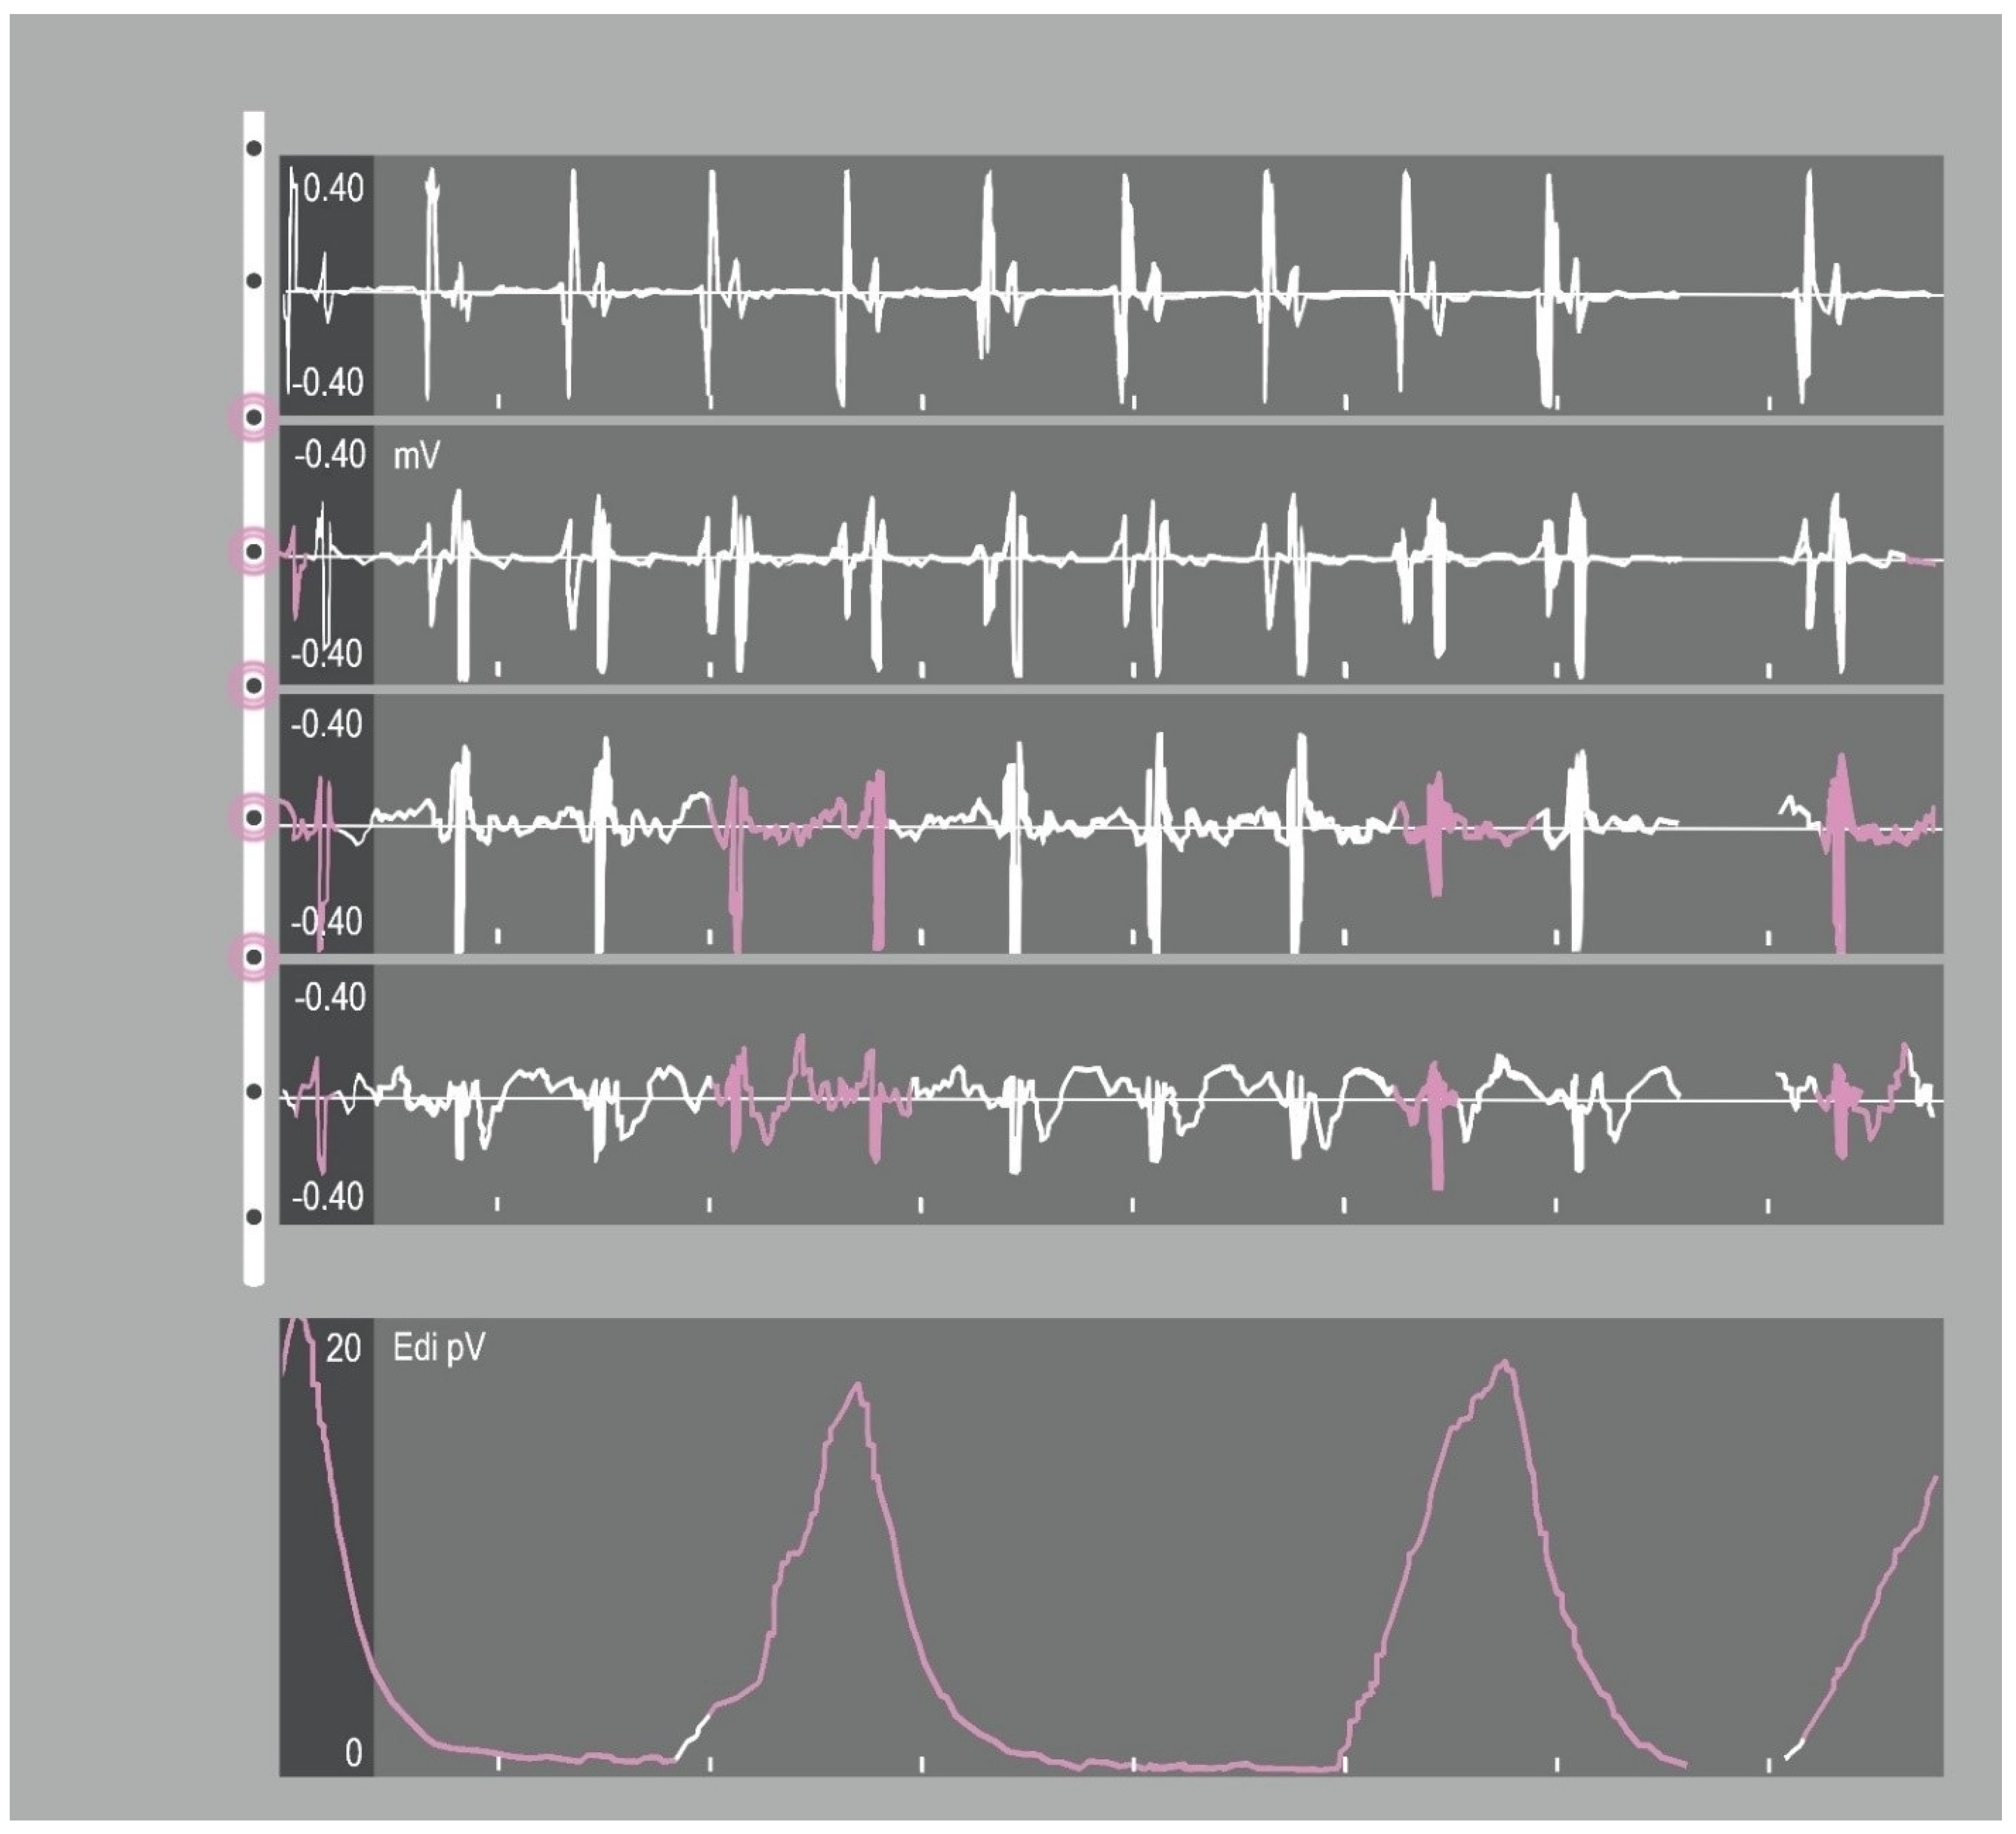

4.1. Basic Principles of NAVA